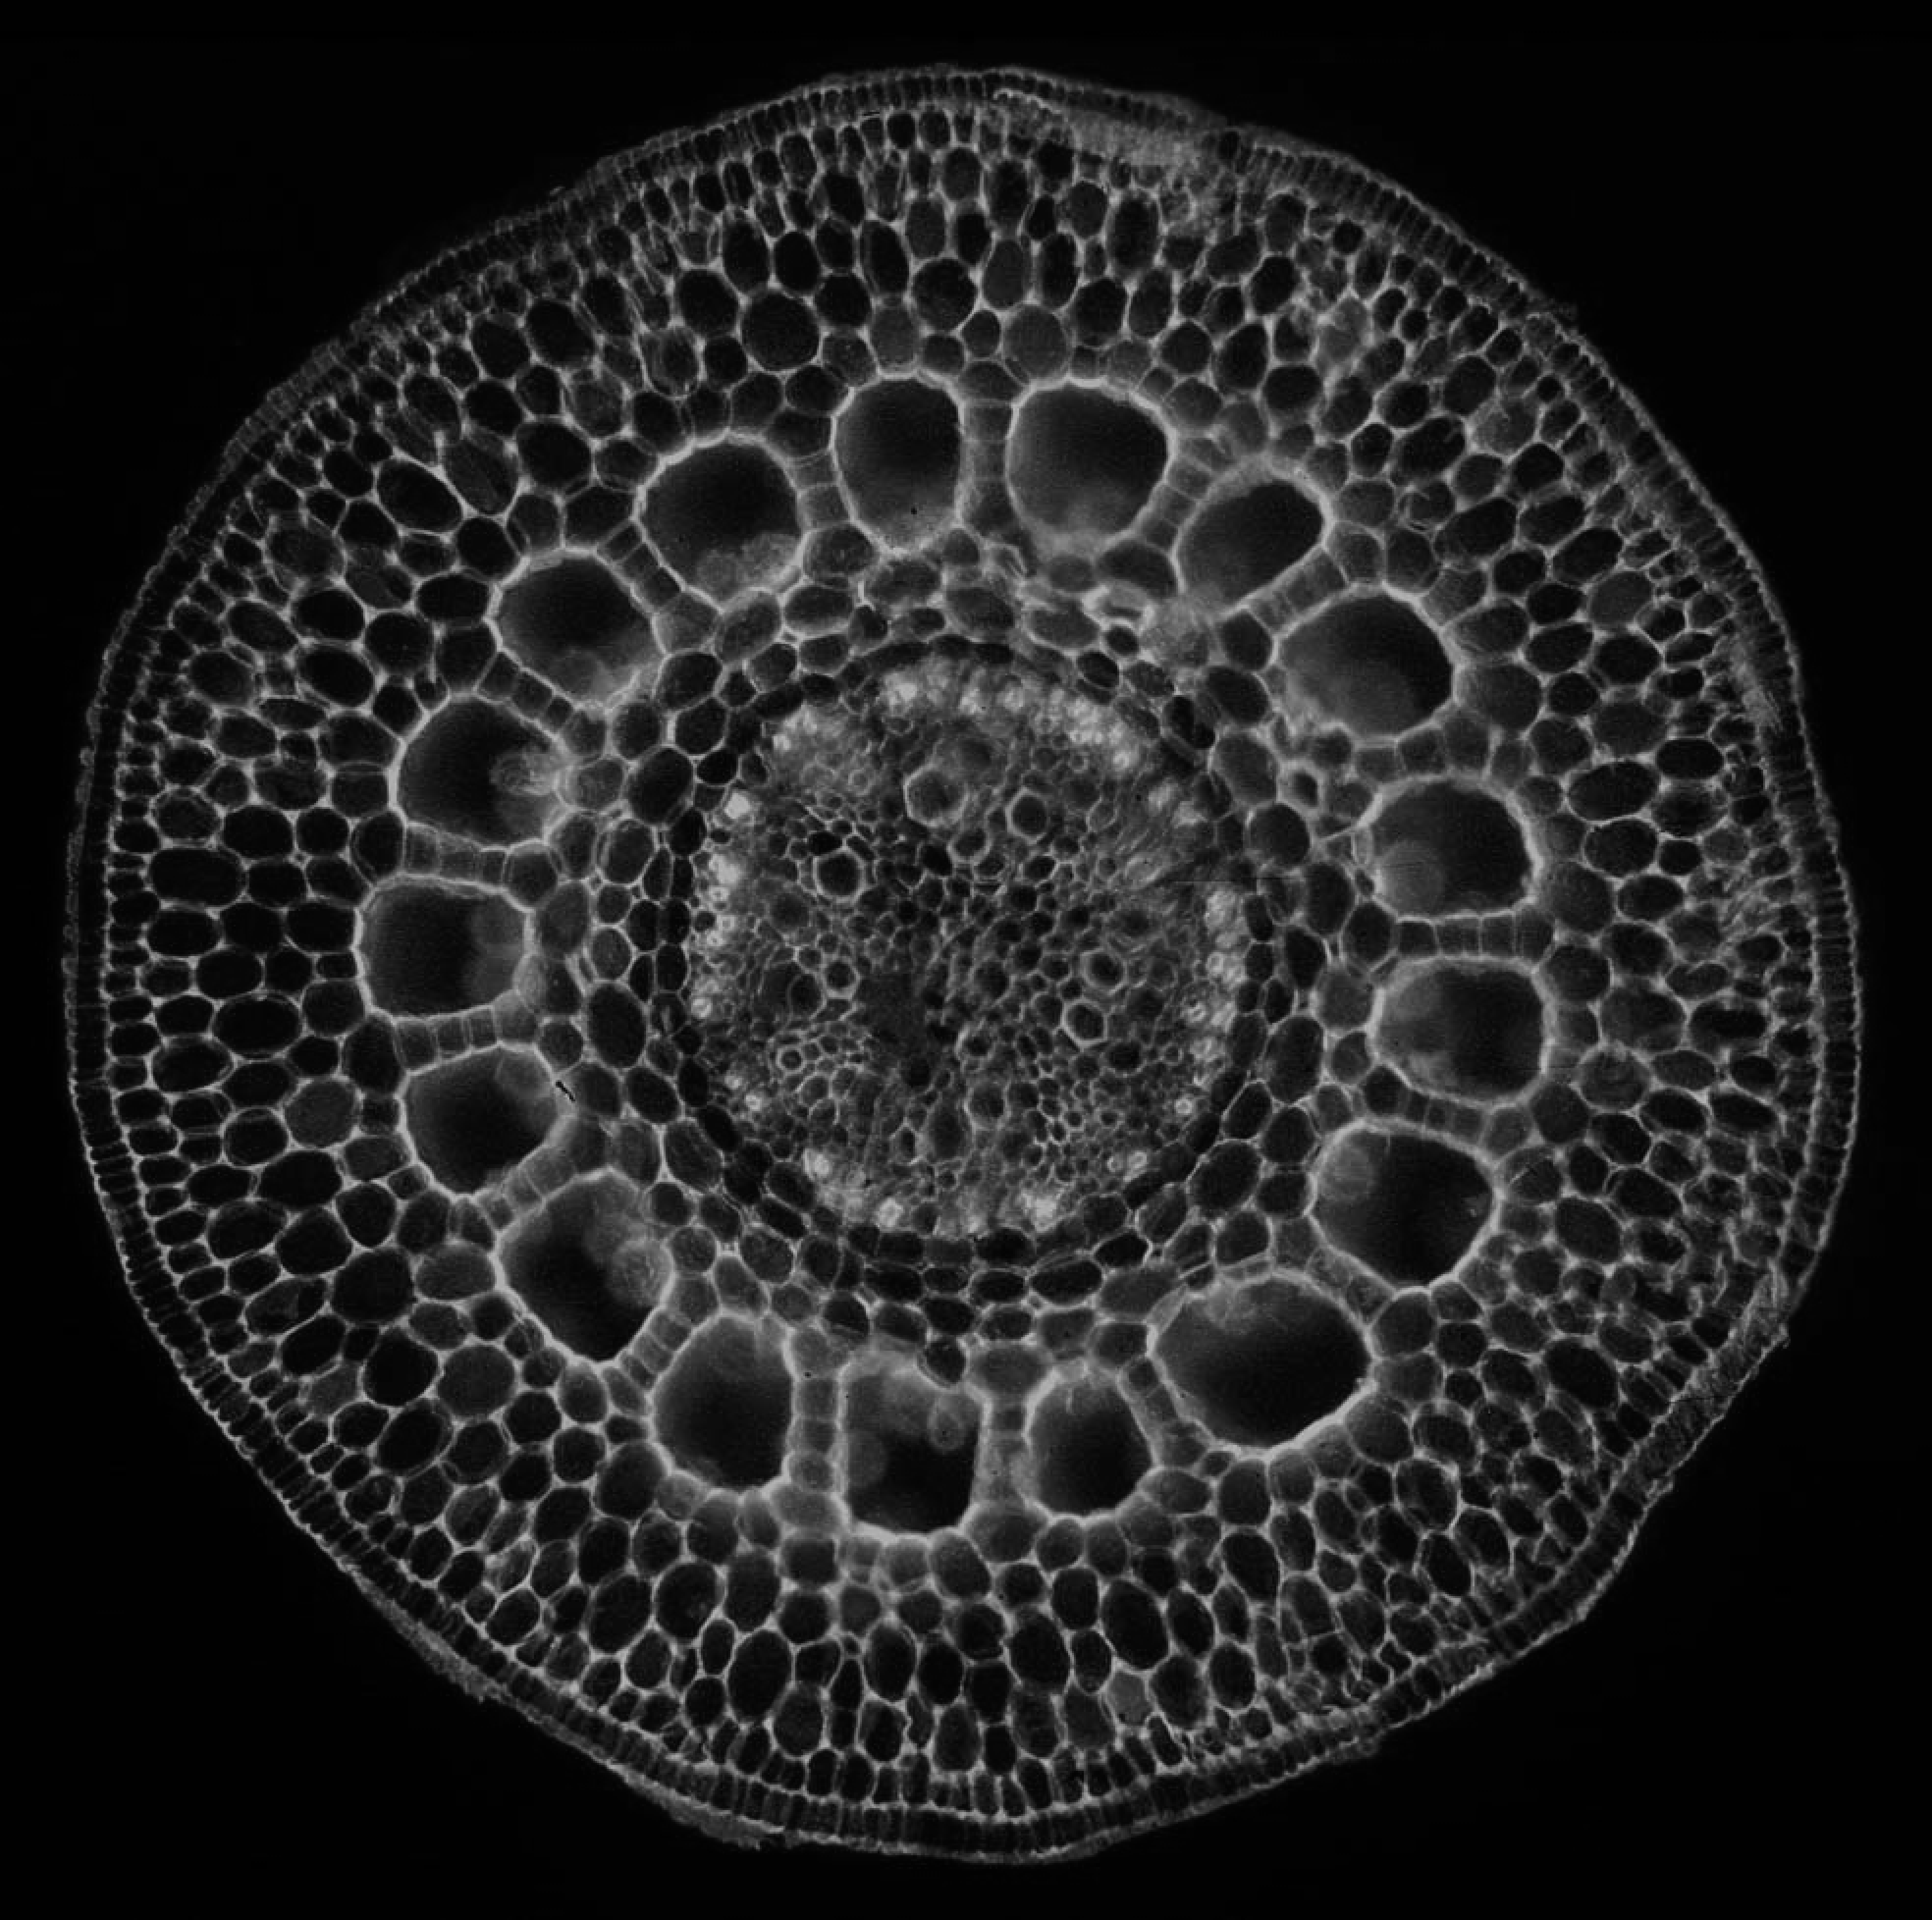

As mentioned above, it is hard (any potentially undesirable) to directly build a GDP from biomedical images. We hence learned the prior from natural-scene images, but validate it here on biomedical images. We first show stability of the present GDP for biomedical images. For this, we collected a small dataset of biomedical images, including X-ray, MRI, electron microscopy, and fluorescence microscopy images. Some examples are shown in Figs. 10 and 24.

9.1 Image naturalization

Remapping the gradient field of any image to match the GDP of natural-scene images, and then reconstructing the output image is called image naturalization, because the output image will have a gradient distribution that matches the one of natural-scene images. The naturalized output image hence looks more “natural”. The workflow is shown in Fig. 23. Since the GDP correlates with image quality, this makes the image look more appealing. We hence propose to use image naturalization as an alternative to histogram equalization when displaying images to a human observer. Image naturalization enhances contrast by solving Eq. 2 with hard GDP constraint. Some examples of microscopy images (left tile of each panel) and their naturalized versions (middle tiles) are shown in Fig. 24 along with the naturalness factor of the original image. The histogram-equalized images are shown in right tiles for comparison. The first row shows four fluorescence-microscopy images. The second row shows three electron-microscopy images and one fluorescence image. All images were collected from publicly accessible web pages; credits are in parentheses. Here we use the simple linear function, amounting to a straightforward rescaling of the image, albeit with a good, “natural” scale factor as determined by the GDP. In all cases. the naturalized image looks more appealing than the histogram-equalized image, and suffers from less background artifacts.